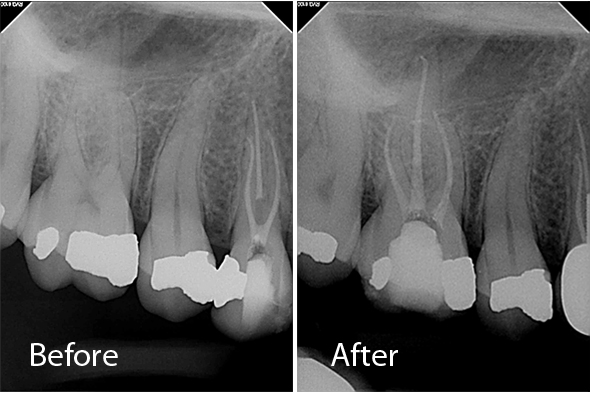

These X-ray images demonstrate the quality and precision of Dr. Portugeys' endodontic procedures. Click any image to view it larger.

Retreatment Premolar